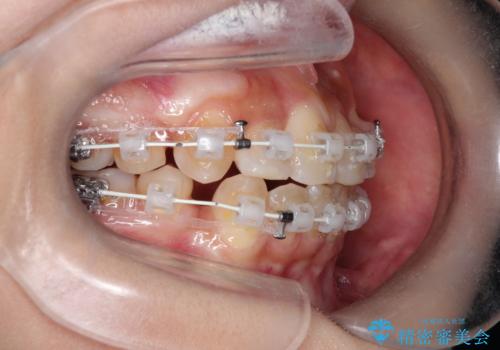

重度の歯並びの乱れを改善|上下4本抜歯と審美ワイヤー矯正で美しい歯列へ

- 患者様は、歯並びのガタガタ(重度の叢生)を改善したいとのことで来院されました。診察すると、歯列のスペース不足が著しく、前歯が重なり合い、噛み合わせにも影響が出ている状態でした。歯をきれいに並べるためには抜歯によるスペース確保が不可欠と判断し、上下の小臼歯4本を抜歯したうえで、目立ちにくい審美ワイヤー矯正(白いワイヤーと透明ブラケット)を用いた治療計画を立てました。

抜歯によって歯を動かすためのスペースを確保。その後、審美ワイヤー矯正を用いて歯を1本ずつ適切な位置に誘導しながら、噛み合わせのバランスも整えていきました。時間はかかりましたが、ガタガタの歯並びがきれいに整い、機能的にも審美的にも満足のいく仕上がりとなりました。患者様からは「歯並びが劇的に改善し、見た目だけでなく噛みやすさも向上した」と喜びの声をいただきました。